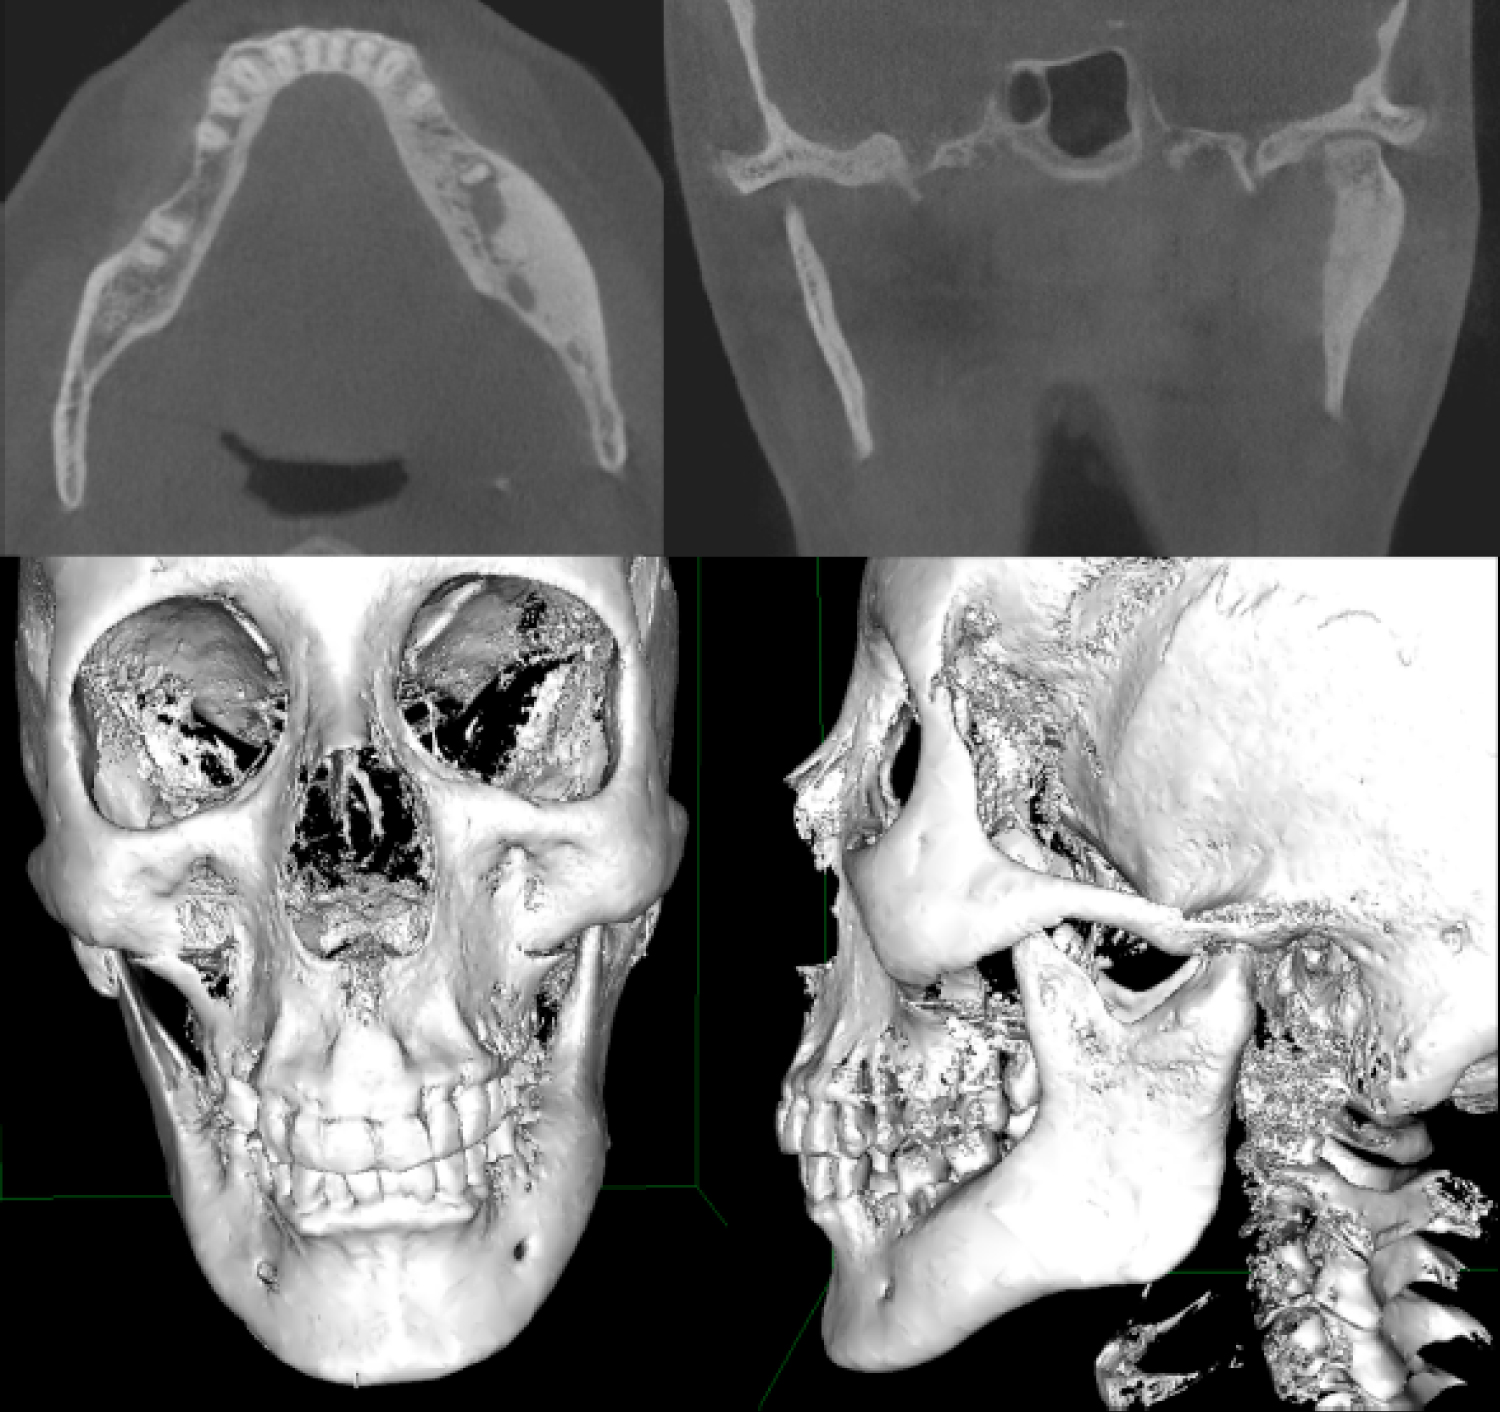

36-year-old female patient, without relevant medical history, was referred to the Maxillofacial Surgery Unit of the Hospital del Salvador (Santiago, Chile), for progressive increases in volume (six years of evolution) at the level of the mandibular body and left preauricular area, painless, well defined and of hard consistency (Figure 1). The patient complains of paresthesia at the level of the left labial commissure, and sounds in the left temporomandibular joint when she eats. The mouth opening is normal, without deviations, and no significant occlusal discrepancies were detected. The skin and oral mucosa of the affected areas appear healthy. A history of local trauma, infection, or some other causal factor was ruled out. A craniofacial computed tomography scan is requested, which shows the presence of three hyperdense areas with net edges and pedicled base, each one with an average size of 20 mm in diameter, compatible with peripheral mandibular osteomas. One is located at the level of the left mandibular body, very close to the exit of the mental nerve, another is located on the lateral aspect of the left mandibular condyle and finally the other is located on the internal aspect of the left mandibular condyle. Cortical perforation and periosteal reaction are not observed (Figure 2).

Figure 2: Pre-operative study. Axial and coronal sections of computed tomography show the different osteomas, both at the body level and the left mandibular condyle. Frontal and lateral views of three-dimensional reconstruction, showing the size and exact location of the mandibular osteomas. View Figure 2